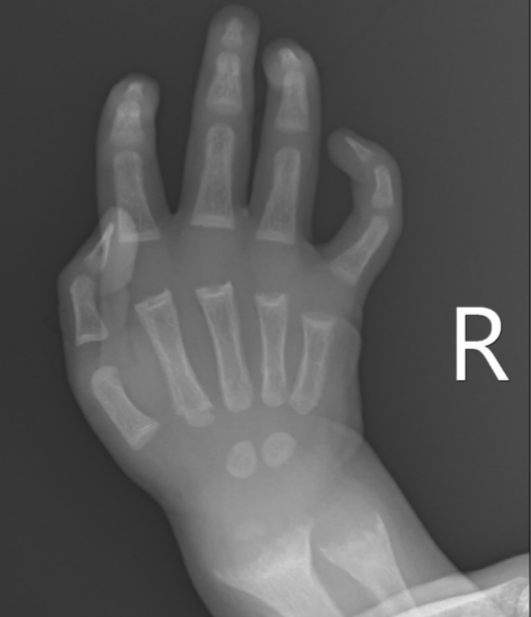

What is seen on X-rays of a rickets patient?

Bowed legs and widened wrists due to metaphyseal cupping.

What causes the widening at the metaphysis in rickets?

Accumulation of non-mineralized bone tissue.